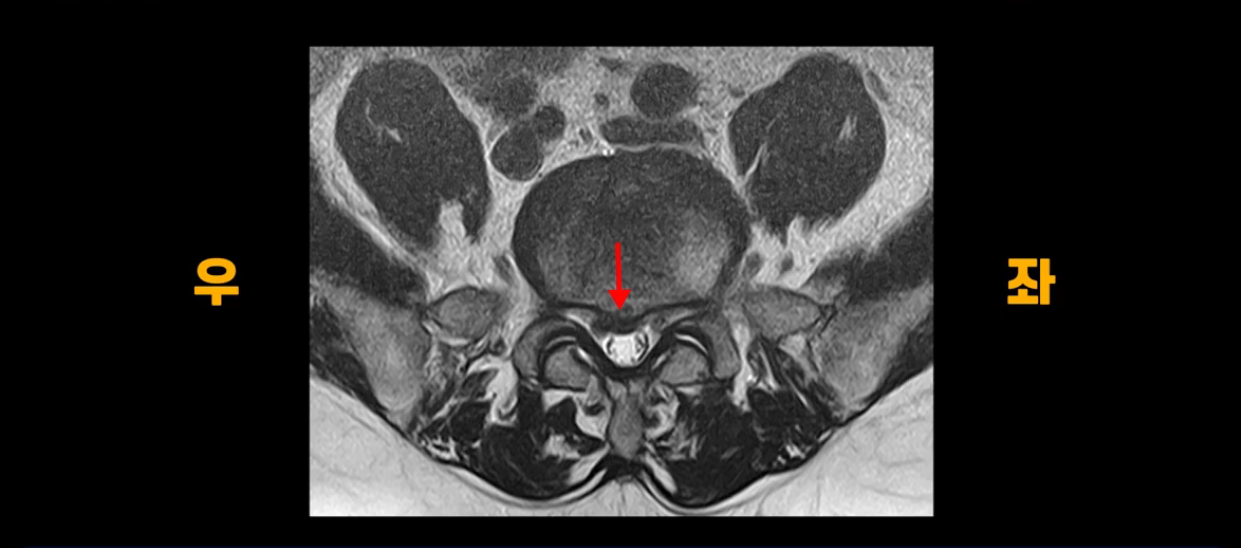

단면을 보면 중앙 오른쪽으로 밀려 나왔는데 파열이 아주 심하지는 않습니다.

아주 심한 상태가 아니라서 방사통만 있지 마비, 즉 힘 빠짐은 없는 상태입니다. 이 정도의 크게 심하지 않은 디스크 탈출 정도라면 신경 주사 맞고 버티다 보면 좋아질 수도 있지만, 이 환자분은 보존한 지 10개월 후에 증상이 더 나빠집니다. 왜 그럴까요? 신경 주사도 전혀 듣질 않는데 어떻게 해야 수술 없이 좋아질 수 있을까요? 지금부터 설명해 드립니다.

이분은 1월에 무거운 걸 들다가 허리디스크가 파열되고 방사통 증상이 나타난 후 10개월 동안 많은 허리디스크 환자가 하는 전형적인 보존 치료 방법을 따라 합니다. 신경 주사, 신전 운동, 허리 구부리지 않기, 걷기 운동 등 이런 방법들을 열심히 하면서 무려 10개월의 시간을 보내지만, 방사통은 오히려 더 악화됩니다. 그 이유는 뭘까요? 저희가 수많은 설명 영상, 치료 후기 영상을 통해서 방사통으로 아픈 사람들이 몇 달씩 버티다 보면 몸이 다 틀어져 버린다고 말씀드렸습니다. 몸이 뒤틀리게 되면 한 달 정도면 가라앉아야 할 신경의 염증이 가라앉지 않고 흡수가 되어야 할 밀려 나온 디스크 수핵도 흡수가 안 된다고 설명해 드렸습니다. 다리 한쪽이 아프니까 안 아프려고 몸을 하루 종일 비틀고 있는데 거기다가 신전 운동하고 신전 자세 한다고 허리에 힘을 주고 있고, 허리를 구부리지 않으려고 하루 종일 허리를 뻣뻣하게 하고 있으니까 허리가 완전히 굳어버리면서 몸이 뒤틀리는 겁니다.

몸이 완전히 틀어져 버린 겁니다. 이렇게 몸이 뒤틀리니까 보존 치료 10개월 후에는 한쪽 팔이 저리는 목디스크 증상까지 생기게 됩니다.

본인은 10개월간 보존 치료 열심히 잘했다고 생각했는데 결국은 다리 방사통은 더 심해지고 없던 목디스크 증상까지 생겼습니다. 허리와 골반 근육들이 경직되고 굳어버리면서 몸이 틀어지니까 보존 치료 백날 해봤자 좋아지질 않는데 신경이 눌려 있다는 데만 생각이 꽂혀있어서 최후의 수단으로 수술 받을 생각만 합니다. 이렇게 근육이 심하게 경직되고 굳어버리고 뒤틀리면 디스크에 가해지는 압력이 증가되어 수술 후에도 재파열 가능성이 높아집니다. 여러분이 주위에 척추 수술 후도 지속적으로 허리가 뻐근하면서 상태가 안 좋은 분들 보신다면 그건 바로 수술의 문제가 아니라 허리 근육 기능들이 전부 다 망가져 있기 때문에 신경을 풀어놔도 안 좋은 겁니다.